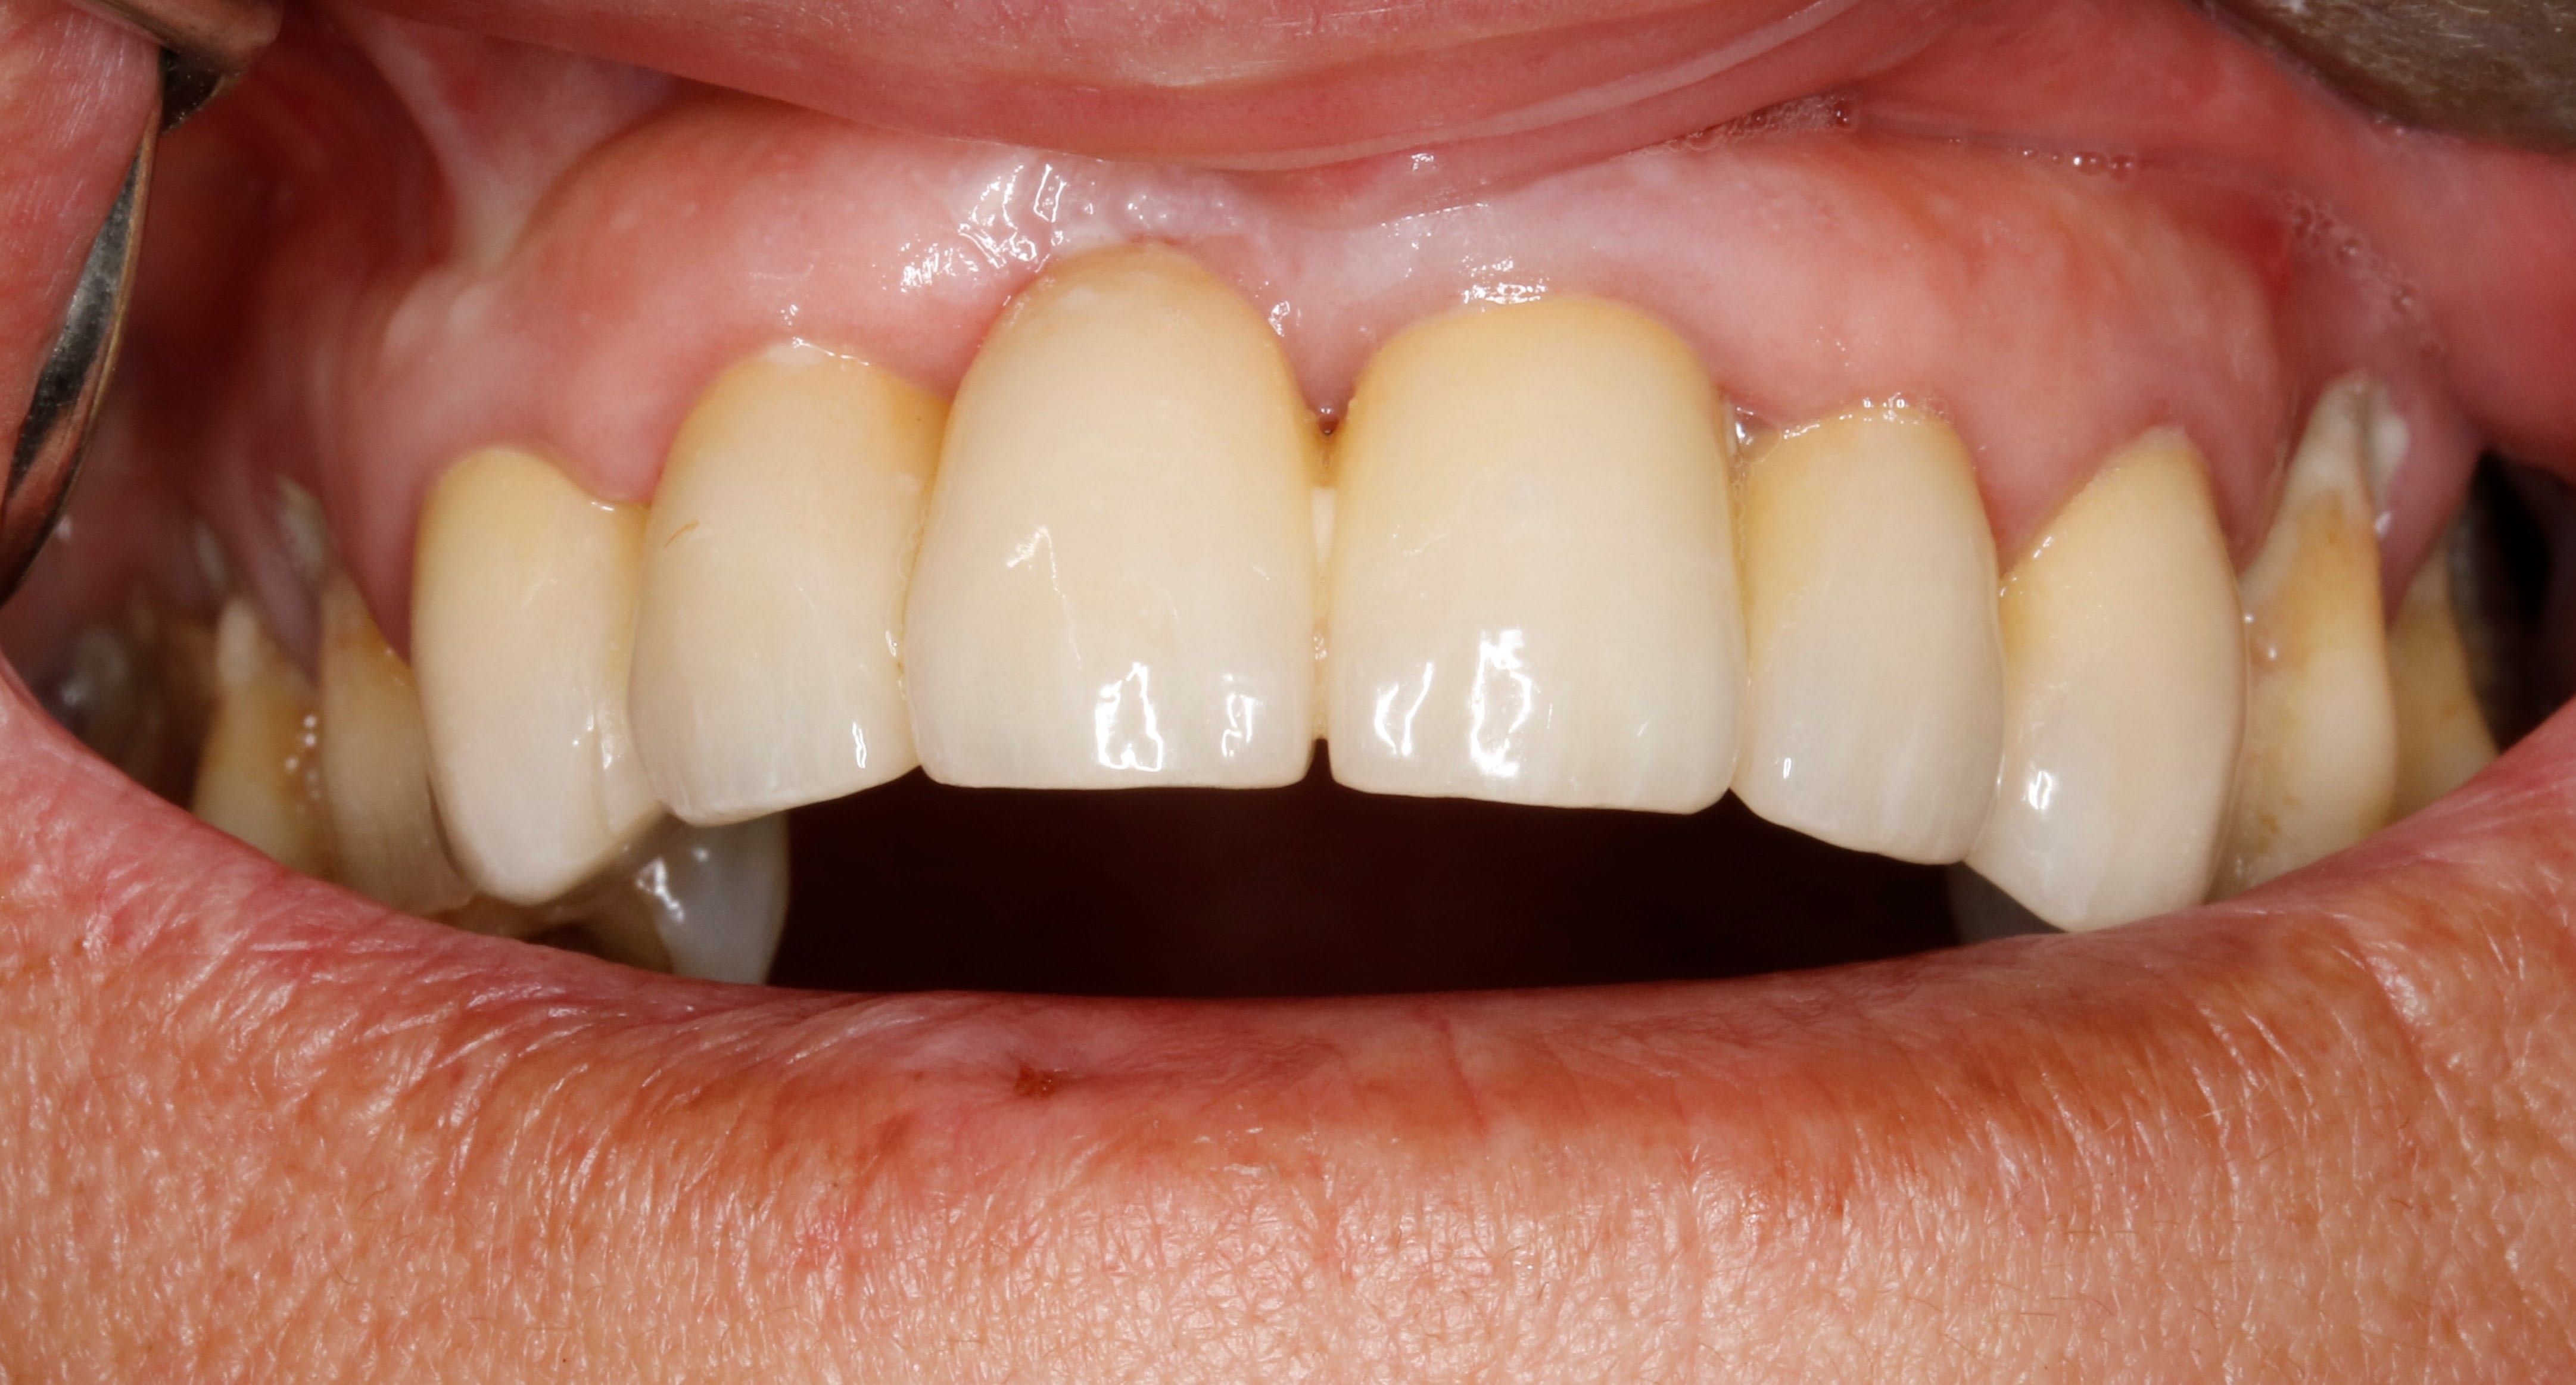

et je l'ai revu hier aprem ( bridge de 2013 ) et ça donne ça .

moralité la paro ç est du pipo , en plus ça m'arrange j'y connais rien :-)))